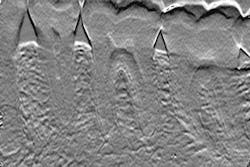

Figure 1 shows how I enhanced the carious lesions in these periapical X-ray images to make them more visible. The technique to acquire the image is no different than with conventional X-ray techniques. The real challenge is to take the time to understand the elements necessary to make the transition: computers, networking, terminology, and electronic image processing (EIP). I hope the articles in this series will make your transition easier and more rewarding.